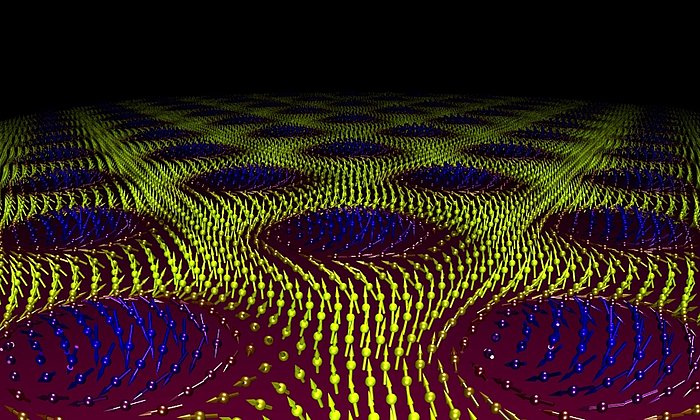

Seine Ergebnisse erstaunen: Nur bei den Proben eines depressiven Patienten, der mit Lithium behandelt worden war, beobachtete Josef Lichtinger eine höhere Anreicherung des Lithium in der sogenannten weißen Substanz. Das ist der Bereich im menschlichen Gehirn, in dem die Nervenbahnen laufen. Der Lithiumgehalt in der benachbarten grauen Substanz war 3-4-fach geringer. Die Lithium-Anreicherung in der weißen Substanz konnte bei mehreren unbehandelten depressiven Patienten dagegen nicht beobachtet werden. Das weist darauf hin, dass Lithium nicht wie andere Psychopharmaka im Zwischenraum der Nervenzellen wirkt, sondern in den Nervenbahnen selbst.

Nun will Josef Lichtinger weitere Gewebeproben an der Forschungs-Neutronenquelle in Garching untersuchen, um seine Ergebnisse zu bestätigen und zu erweitern. Am Ende des Projekts steht eine Landkarte des Gehirns eines gesunden und eines depressiven Patienten, die ortsaufgelöst die Lithiumanreicherung zeigt. So könnte man das Universalmedikament Lithium zukünftig noch zielgenauer und kontrollierter gegen psychische Erkrankungen einsetzen. Die Arbeit wird von der Deutschen Forschungsgemeinschaft (DFG) unterstützt.